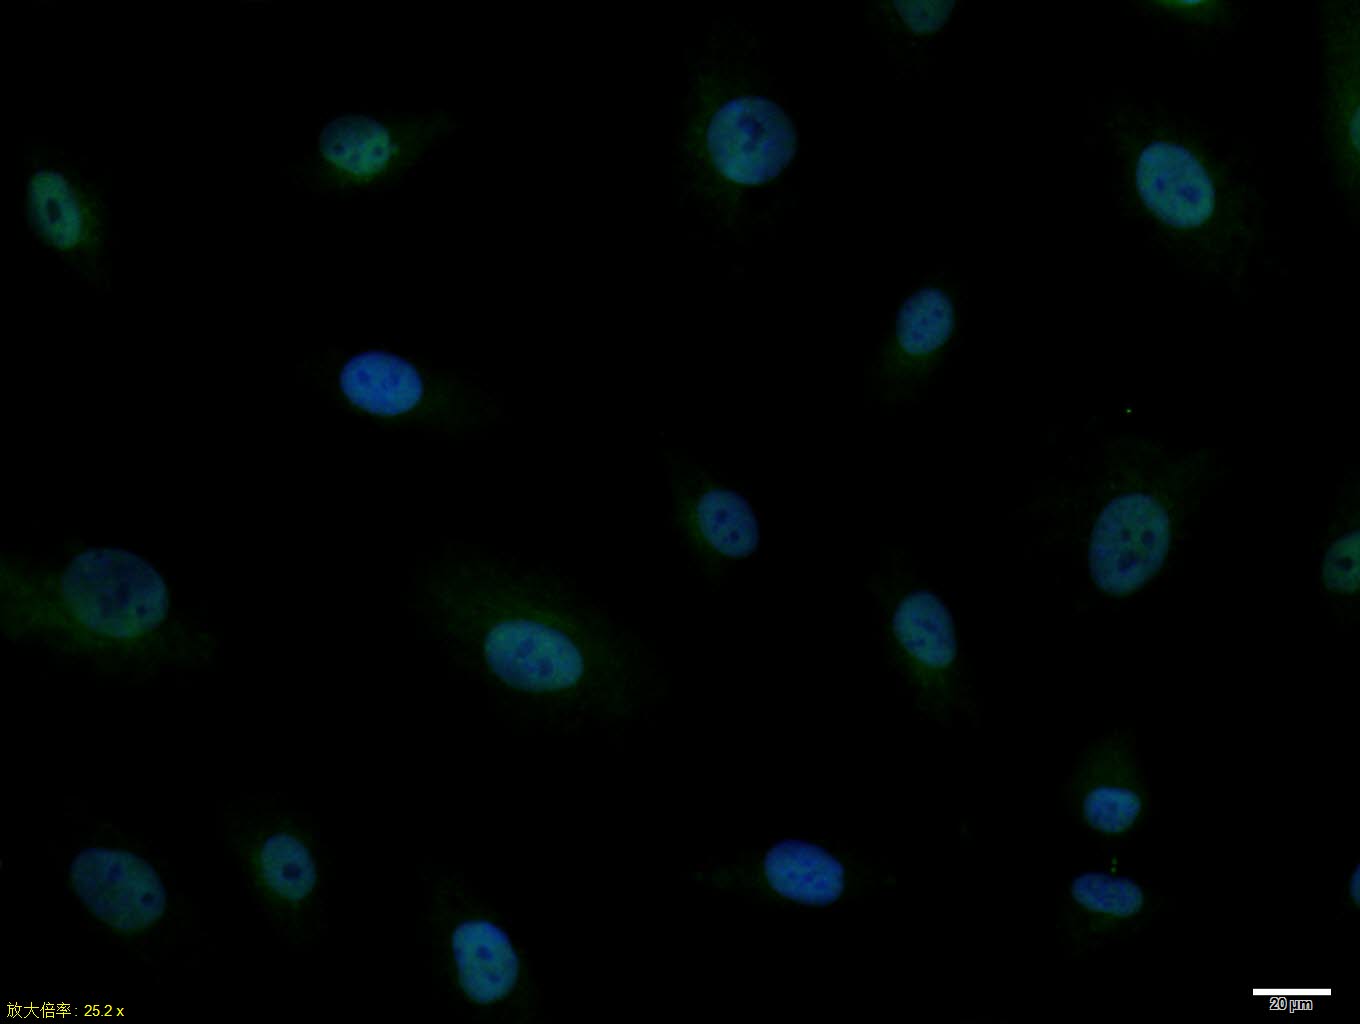

Primary Antibody (green line): Rabbit Anti-MASH1 antibody (bs-1155R)

Dilution: 2ug/Test;

Secondary Antibody : Goat anti-rabbit IgG-FITC

Dilution: 0.5ug/Test.

Protocol

The cells were fixed with 4% PFA (10min at room temperature)and then permeabilized with 90% ice-cold methanol for 20 min at -20℃.The cells were then incubated in 5%BSA to block non-specific protein-protein interactions for 30 min at room temperature .Cells stained with Primary Antibody for 30 min at room temperature. The secondary antibody used for 40 min at room temperature. Acquisition of 20,000 events was performed.